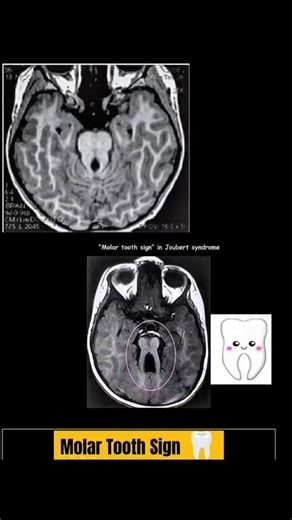

RK NURSE'S HUB on Instagram: "The molar tooth sign (MTS) in radiology refers to a characteristic appearance of the midbrain and hindbrain on an axial Magnetic Resonance Imaging (MRI) scan. It is the pathognomonic imaging feature for Joubert syndrome and related disorders (JSRD). This sign is caused by a malformation in brain development, specifically the absence of normal decussation (crossing over) of the superior cerebellar peduncles. The key features contributing to the "molar tooth" shape ar